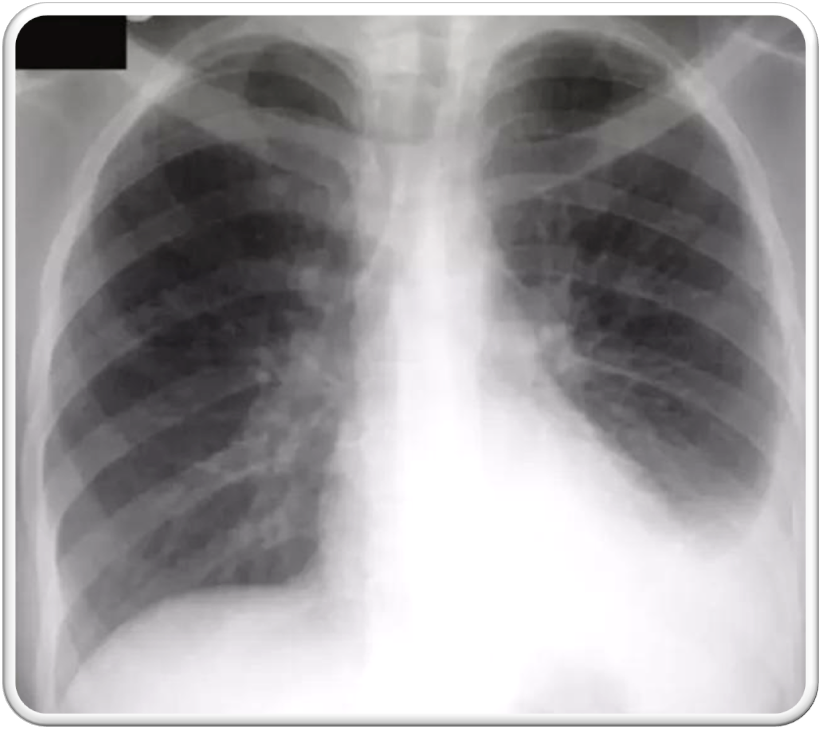

⁠ ⁠Ghon focus may be visualized on the chest radiograph as an airspace opacity

•⁠ ⁠Small tan-yellow subpleural granuloma in the mid-lung field on the right.

•⁠ ⁠Over time, the granulomas decrease in size and can calcify, leaving a focal calcified spot on a chest radiograph that suggests remote granulomatous disease.

• ⁠ ⁠typical of primary tuberculosis in a child

• Airspace consolidation is usually unilateral, is evident radiographically in approximately 70% of children with primary TB.